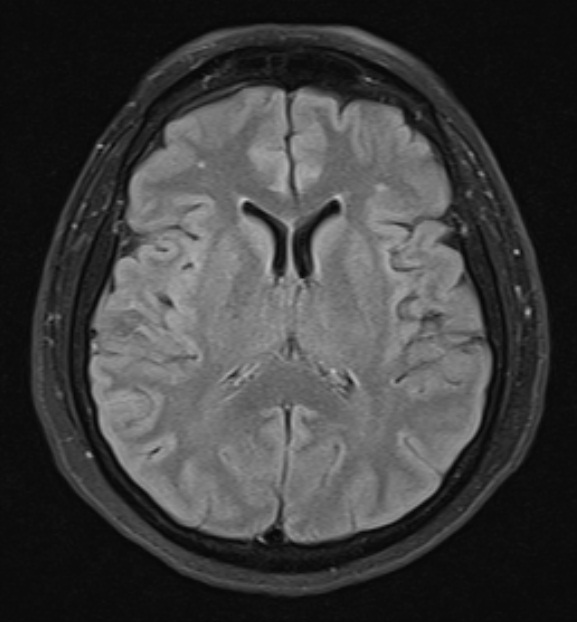

Engineer Team : RESONANCIA MAGNETICA Magnetic Resonance Imaging – Clinical Images Hallazgos por resonancia magnética cerebral de nuestro paciente. M, 21 … Imágenes por resonancia magnética anormales como predictoras de mal … Imágenes por resonancia magnética anormales como predictoras de mal … Lesiones en resonancia magnética (RM) del encéfalo y la médula espinal … Pin en Resonancia Magnética del Encéfalo A) Resonancia magnética cerebral (RMC) mostrando infartos en … Caso 1: Edema cerebral visualizado mediante RM. (A) Secuencia T1 plano … Rascacielos dormir pasta tac y resonancia diferencias retrasar … Pin on Apuntes de Enfermería y T.C.A.E Resonancia magnética cerebral secuencia T2, que muestra lesión … Meningitis aguda en la enfermedad de Behçet | Reumatología Clínica Resonancia magnética coronal normal del cerebro Fotografía de stock – Alamy Imágenes de resonancia magnética, la imagen de la cabeza en diferentes … Resonancia magnética cerebral A) protocolo T1 sagital (Caso 1). Se … Resonancia magnética cerebral. Secuencia T1 corte sagital. Atrofia … Resonancia magnética de cerebro, cortes axiales, secuencias T2. Señal … Resonancia magnética de cráneo. A y B) Cortes axiales FLAIR … Resonancia magnética (RM) de cerebro, corte axial ponderado en T2: la … RM cerebral: Interpretación paso a paso | Kenhub Resonancia magnética de cerebro, cortes axiales, secuencias T2. Señal … De Resonancia Magnética De Cerebro Foto de archivo – Imagen de arteria … Top 107+ Imagenes de resonancia cerebral normal – Destinomexico.mx -Imagen por resonancia magnética del cerebro. a) Cortes sagital y axial … resonanCia magnétiCa Cerebral donde se observa hiperintensidad a nivel … MRI (Imagen de resonancia magnética) – Tomografía computarizada de la … Meningioma – NCI Imágenes por resonancia magnética coloreadas del cerebro sano del … Resonancia magnética cerebral en secuencia FLAIR, que muestra lesiones … Contraste resonancia magnetica cerebral – senturinthegreen Relación de los espacios de Virchow-Robin con la enfermedad de … Gliomatosis cerebral – Instituto Nacional del Cáncer Pin en Neurology. Recomendaciones para la utilización e interpretación de los estudios de … Fotografía De La Proyección De Imagen De Resonancia Magnética Del … atmósfera Dirigir Cumplir anatomia resonancia magnetica Desarrollar … Pin en #MEDICINA,#SALUD Resonancia magnética de la nasofaringe De Resonancia Magnética De Cerebro Foto de archivo – Imagen de polilla … Atrofia cortical global de predominio parietal en la Resonancia … Resonancia magnética cerebral | Download Scientific Diagram Neuroblog: Resonancia magnética cerebral en la trombosis crónica de … De Resonancia Magnética De Cerebro Imagen de archivo – Imagen de … ¿Cuáles son los riesgos de la resonancia magnética? – Integra Salud … Resonancia magnética cerebral al decimocuarto día de ingreso: área … Resonancia magnética. Corte axial mostrando área infartada en el … Resonancia magnética cerebral del paciente AV evidenciando lesiones en … -Ressonância magnética de encéfalo mostrando múltiplas imagens … Resonancia magnética cerebral secuencia FLAIR (Fluid Attenuated … Resonancia magnética cerebral con protocolo de epilepsia, en sección … Resonancia magnética cerebral en corte sagital. Se observa una evidente … Resonancia magnética craneal en la que se evidencian lesiones … Logran visualizar el cerebro a detalle más completo tras una resonancia … Así decide el cerebro la severidad de un castigo De Resonancia Magnética De Cerebro, Imagen de archivo – Imagen de … A) Resonancia magnética cerebral; Secuencia Tof: oclusión de arteria … Un estudio asocia la ansiedad con la aparición rápida del Alzheimer IMÁGENES DE 18 F-PR04.MZ PET FUSIONADA CON RESONANCIA MAGNÉTICA … Imágenes por resonancia magnética anormales como predictoras de mal … Tumores de la región pineal – Instituto Nacional del Cáncer Epilepsia: una historia de voces y fantasmas | Neurología Contribución de las imágenes de resonancia magnética por tensor de … Resonancia magnética secuencia T2 plano coronal de quiste epidermoide … Resonancia Magnética Cerebral del paciente: a. Aumento de… | Download … Resonancia magnética cerebral 2022 Síndrome de hemiconvulsión-hemiplejía-epilepsia. Seguimiento de un caso … Enfoque Radiologico: La resonancia magnética permite detectar lesiones … Resonancia magnética craneal T1 con contraste que muestra angiomatosis … guidewiz – Blog Resonancia magnética cerebral, secuencia SWI. Ribete hipointenso en la … resonAnCiA mAgnétiCA de ColumnA Con gAdolinio. Corte sAgitAl en t1 de … SEMANA 12: FUNDAMENTOS DE RESONANCIA MAGNÉTICA NUCLEAR. INDICACIONES Y … DIAGNÓSTICO DE ESCLEROSIS MÚLTIP Magnetic resonance imaging of the brain – Alchetron, the free social … Resonancia magnética de órbitas | Instituto Radiológico Dr. E Castillo Alteración de la marcha en un paciente post-trasplante hepático Resonancia magnética cerebral de un paciente sano (Ay B) y paciente que … Utilidad de la resonancia magnética craneal para el diagnóstico de la … Resonancia Magnética Del Cerebro El Tumor Cerebral Foto de stock y más … De Resonancia Magnética De Cerebro Imagen de archivo – Imagen de … ABDALLA RADIOLOGIA: NEURINOMA ACUSTICO Atrofia cortical global de predominio parietal en la Resonancia … Resonancia Magnética : Producción de la imagen MRI Brain Scan — Stock Photo © Bunyos30 #18724051 Mri (imagen de resonancia magnética) Monitor con imagen de captura de … Tomografía computarizada vs resonancia magnética: diferencia y … Tumores Cerebrales – Unidad de Neurocirugía RGS Resonancia magnética de la columna, sección sagital. Observe los discos … La resonancia magnética, una técnica imprescindible en el diagnóstico … Perfusión Cerebral por Resonancia Magnética | ¿Qué es? ¿Necesita Contraste? Resonancia Magnética Cerebro A: resonancia magnética, T2 coronal preoperatoria; se observa lesión en … Resonancia magnética cerebral — Foto de stock © Bunyos30 #27340623 La resonancia magnética se perfila como detector de mentiras | Futuro … Resonancia magnética cerebral en T1 con gadolinio, cortes axial (a … MRI brain : show brain tumor at right parietal lobe of cerebrum — Stock … NEUROIMÁGENES EN ENFERMEDAD DE PARKINSON: ROL DE LA RESONANCIA …